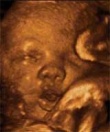

Uno de los avances tecnológicos dentro de este campo, son las ecografías en cuatro dimensiones que permiten observar al feto con claridad y ser testigos de sus movimientos, gestos y sollozos. Además de apreciarse con claridad una mejor vista de la facie del feto lo cual aparte de diagnosticar defectos del desarrollo embrionario como el Labio Leporino, le proporciona a los futuros padres una vista panorámica del aspecto que tendrá el recien nacido.